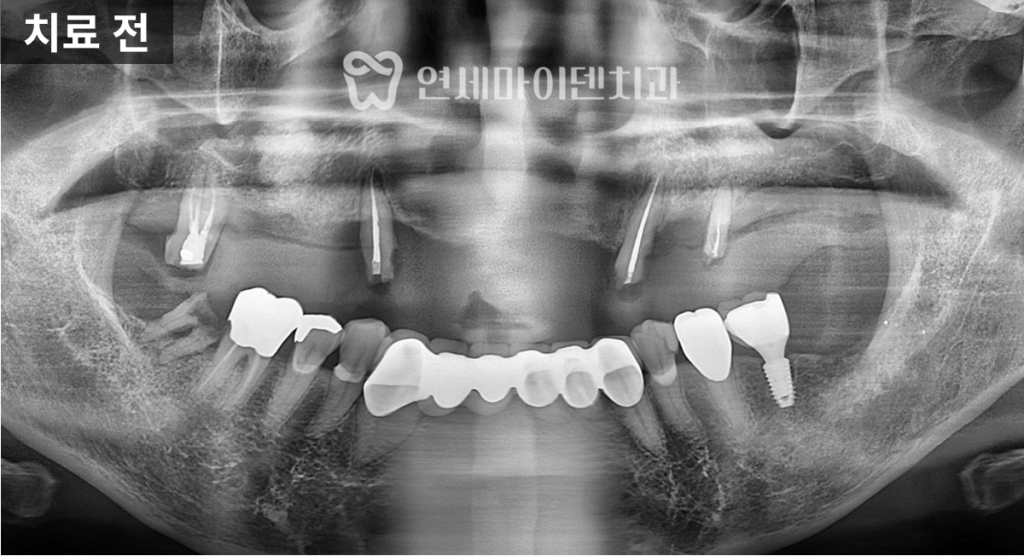

자세히 살펴보겠습니다.초기 상태와 치료 목표

이번 케이스는

이미 다른 치과에서

임플란트 치료가 시작된 상태로 내원한 사례였습니다.상악 치아는 심하게 손상되어

일부는 틀니 형태로 사용 중이었고,

하악은 앞니 보철 치료가

이미 완료된 상황이었습니다.

정면에서 보면

위 앞니보다 아래 앞니 노출이

더 많은 상태임을 확인할 수 있었습니다.이번 치료의 핵심 목표는

다음 두 가지였습니다.- 전치부, 특히 앞니의 돌출을 개선하는 것

- 위 앞니의 노출 비율을 늘려 외관상 나이가 들어 보이지 않도록 하는 것